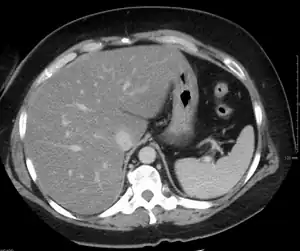

As análises de sangue que traduzem o funcionamento do fígado revelam apenas ligeiras alterações inespecíficas. O diagnóstico será feito com exames que permitam visualizar o fígado, como a ecografia ou a tomografia computorizada, que evidenciam um excesso de gordura no fígado. O diagnóstico confirmatório é feito com a realização de uma biopsia hepática (do fígado), sendo positivo caso mais de 10% da sua massa seja gordura, porém esta confirmação não é, geralmente, necessária.[7]